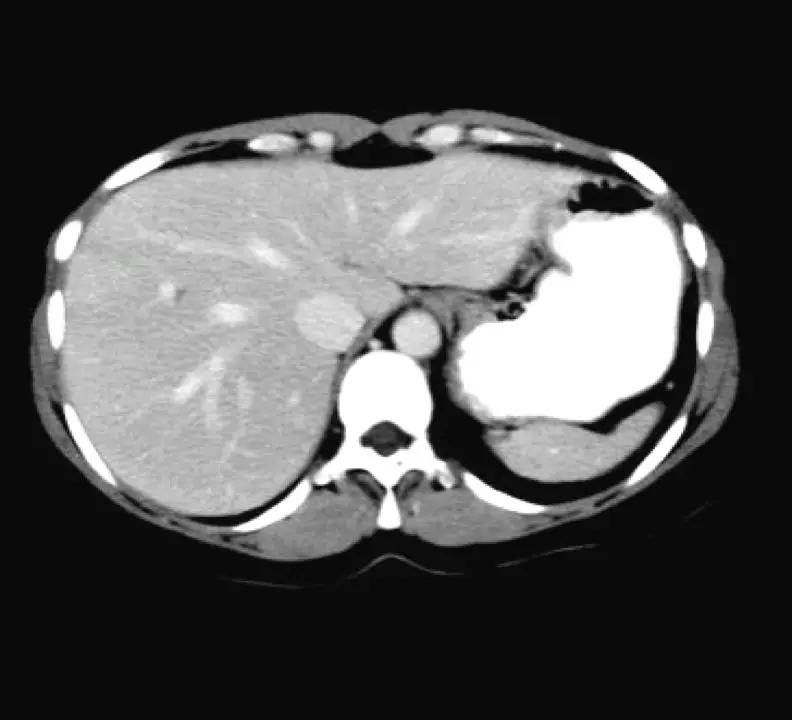

(软组织成像)